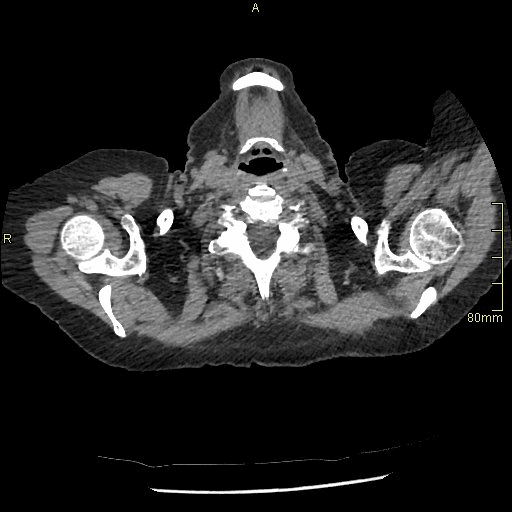

HRCT - Axial Supine Expiration (Soft Tissue Window)